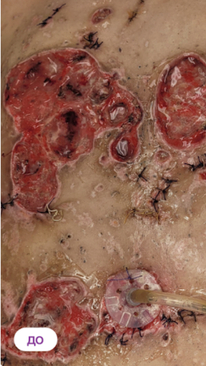

Хронический остеомиелит

Стойкая ремиссия после 4 процедур ФДТ Ревиксан